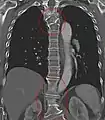

Lumbarization and sacralization

Lumbarization of sacral vertebra 1, seen as 6 vertebrae that do not connect to ribs.

Lumbarization is an anomaly in the spine. It is defined by the nonfusion of the first and second segments of the sacrum. The lumbar spine subsequently appears to have six vertebrae or segments, not five. This sixth lumbar vertebra is known as a transitional vertebra. Conversely the sacrum appears to have only four segments instead of its designated five segments. Lumbosacral transitional vertebrae consist of the process of the last lumbar vertebra fusing with the first sacral segment. [1] While only around 10 percent of adults have a spinal abnormality due to genetics, a sixth lumbar vertebra is one of the more common abnormalities. [2]